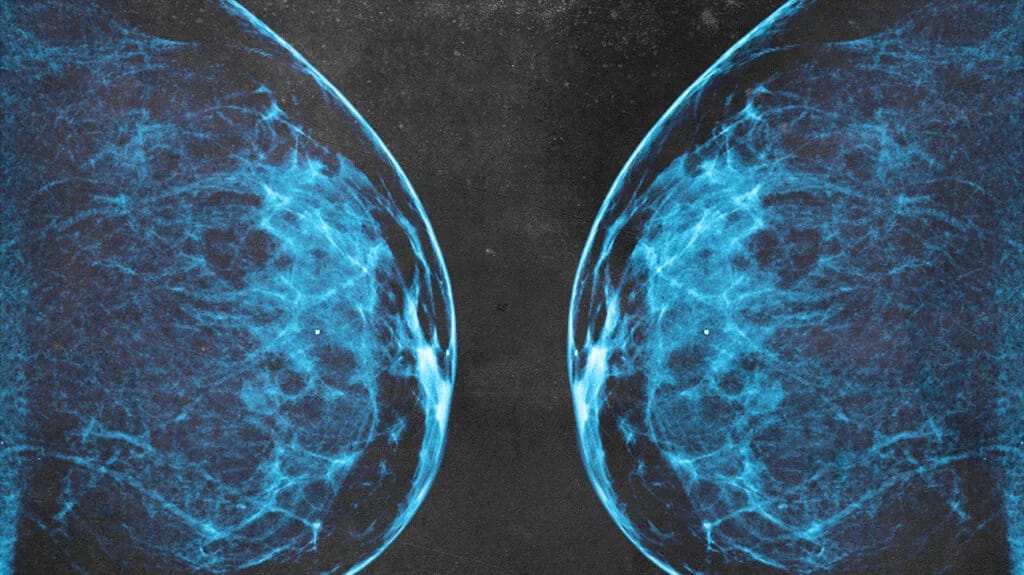

Mammograms have long been the gold standard screening tool for breast cancer. They work by using X-rays to create images of the breast tissue, helping to detect abnormalities, including tumors, at an early stage.

Less effective for dense breasts: Women with dense breast tissue often experience less accurate mammograms because dense tissue and tumors both appear white on the X-ray, making it harder to detect cancer.

It’s also estimated that 20% of breast cancers are missed by mammograms. This number increases to 50% if you have dense breasts. Dense breasts refer to breasts that have a higher proportion of fibrous and glandular tissue compared to fatty tissue. This is a normal variation and can be found in many women, particularly those who are younger, though density can persist in older women as well. Breast density is usually determined through a mammogram, but it’s not something that can be felt during a physical exam.